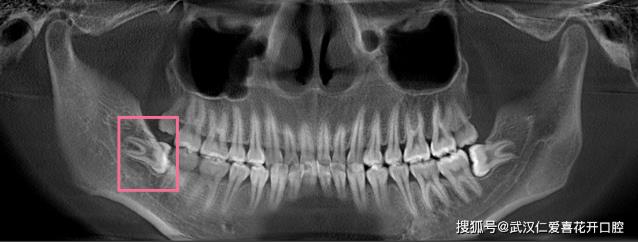

医生没有骗人,她在几年后还是去拔了,并且她的智齿长成了獠牙,往内嵌得非常深,和神经线几乎是脸贴脸,拔牙难度系数★★★★★

红圈里的那根白线就是神经线